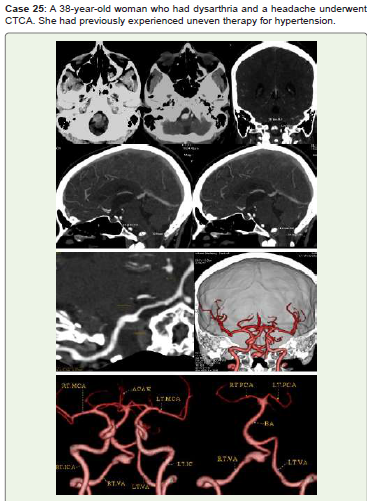

In the arteries of the circle of Willis, saccular aneurysms usually affect the following arteries in order of frequency [4]. The middle cerebral artery (20%) (Figure1, Figure 2, Figure 9, Figure 13, Figure 24), the anterior communicating artery (30%) (Figure 3, Figure 4, Figure 7, Figure 10, Figure 11, Figure 12, Figure 23), the internal carotid artery (8%) (Figure 6, Figure 13, Figure 14, Figure 15, Figure 16, Figure 17, Figure 18, Figure 20), and the tip of the basilar artery (Figure 21), Pericallosal anterior cerebral artery (4%) (Figure 8, 12) and posterior inferior cerebellar artery (3%). Fusiform aneurysms (Dolichoectasia) (Figure 25) are long, spindle-shaped arterial dilations that may be linked to non-atherosclerotic pathology, such as connective tissue disorders, or atherosclerotic vascular disease [3]. Ectatic sinuous cerebral arteries, which are most commonly found in the vertebrobasilar system, give rise to dolicoectasia, which can have a diameter of several centimeters. Although symptoms of brainstem or cranial-nerve compression are typically present in these situations, they are not typically linked to SAH [5]. A ruptured artery or cystic medial necrosis are the causes of dissecting aneurysms. Thirty percent of affected people develop multiple aneurysms [5] - According to the Unruptured Cerebral Aneurysm Study [6], aneurysms should be classified as small (<5 mm), medium (>5-10 mm), large (>10 mm-25 mm), and giant (>25 mm) based on the maximum dome diameter. A neck diameter greater than 4 mm or a dome-to-neck ratio less than 2 were indicative of a wide-neck aneurysm.

Figure 25:An oval hyperdensity is visible anterior to the medulla in CT axial

non-contrast (A). A large right vertebral fusiform aneurysm (Dolichoectasia)

measuring 12.8x12.8x11.9 mm with a posterior intramural thrombus measuring

11.1x5.9 mm is visible in axial, coronal, and sagittal contrast images (B-F),

virtual dissection (G), and 3D-VR images (H, I). Endovascular therapy and

further monitoring were recommended for her.